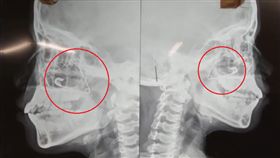

女星許維恩10月大女兒日前傳出誤吞別針,出現臉色慘白...

許維恩女兒誤吞別針 醫示警這4物最危險

藝人許維恩在2021年閃嫁小6歲王家梁,去年他們也生...

女兒誤吞別針缺氧吐血絲 許維恩:好失敗

藝人許維恩2021年與藝人王家梁結婚,去年6月寶貝女...

嬰喉嚨卡2cm別針 臉脹紅嚎哭險死

新衣服吊牌上的別針,差點要了男嬰的命!台中一名十個月...